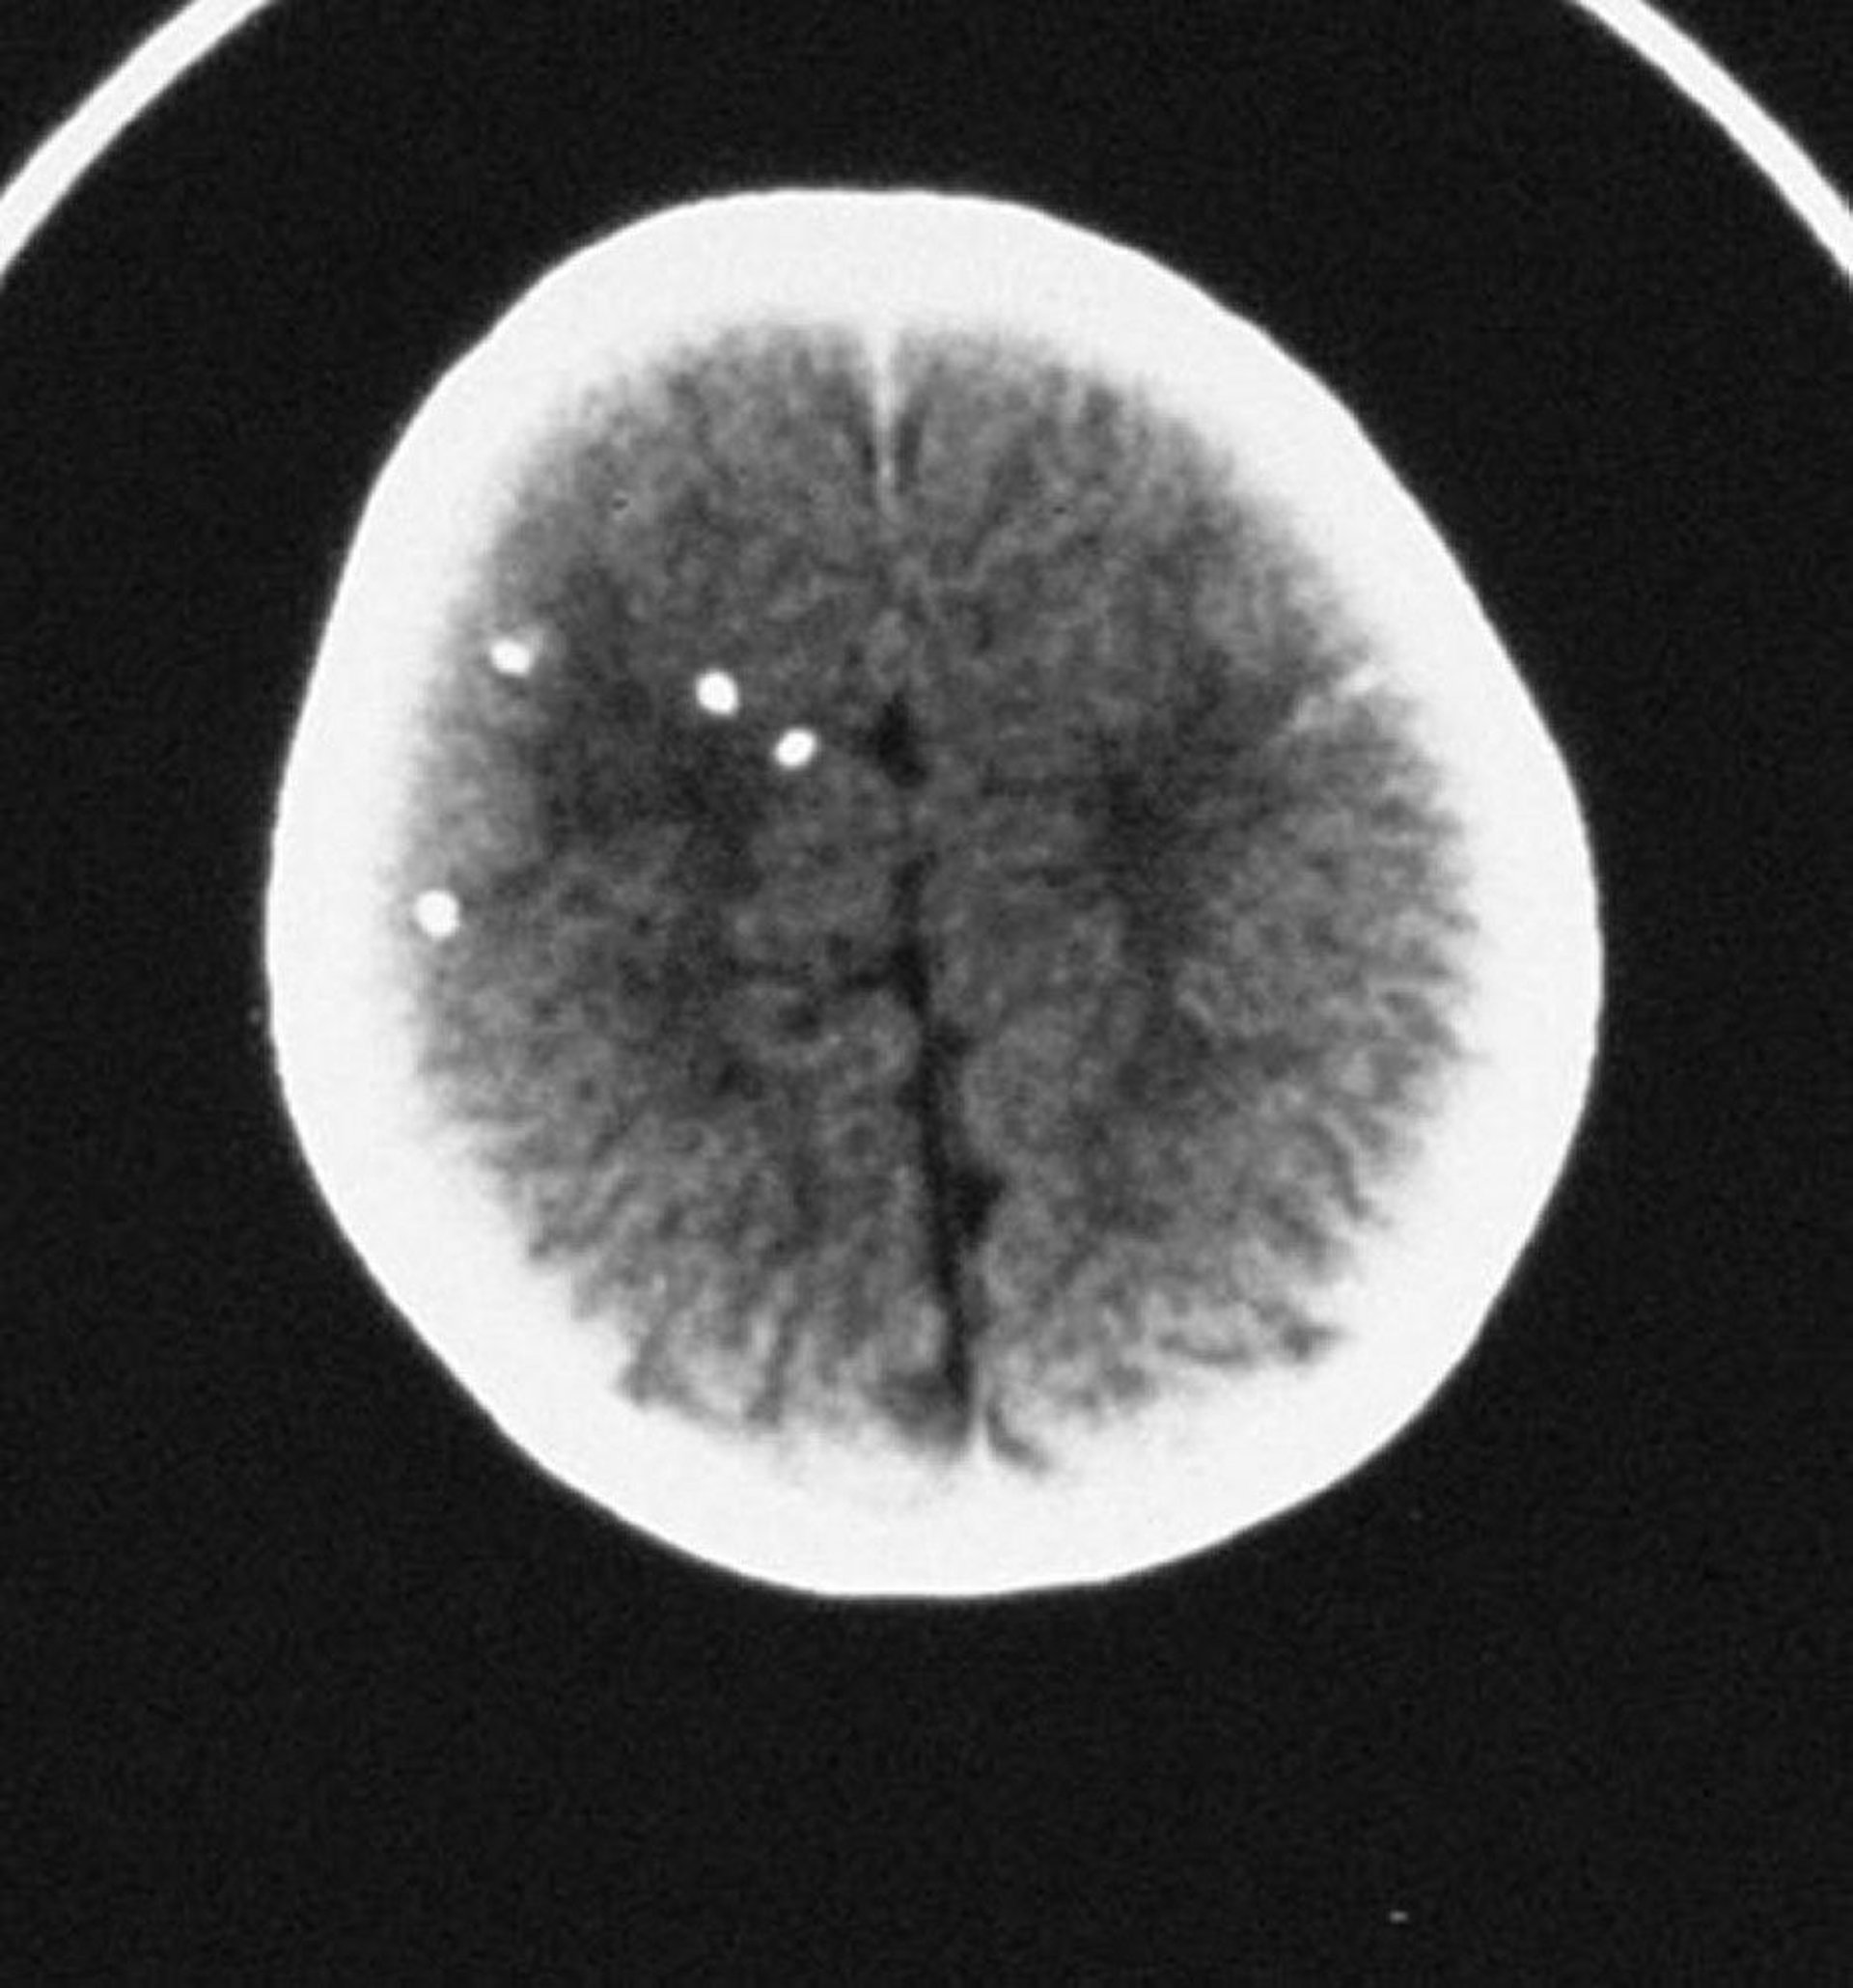

Congenital Toxoplasmosis

This CT scan shows scattered intracranial calcifications.

By permission of the publisher. From Demmler G: Congenital and perinatal infections. In Atlas of Infectious Diseases: Pediatric Infectious Diseases. Edited by CM Wilfert. Philadelphia, Current Medicine, 1998.